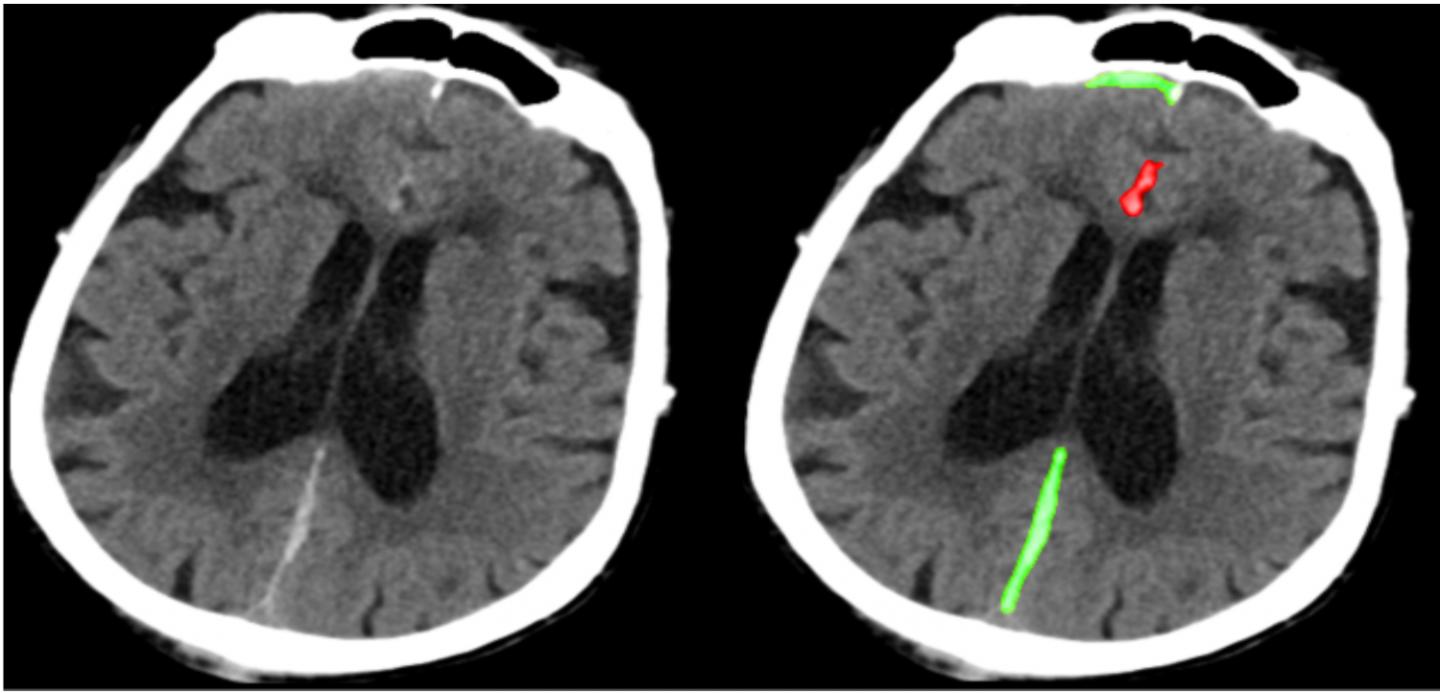

Researchers report an algorithm that could potentially improve diagnosis of neurological emergencies. Computed tomography (CT) scans of the head are used to rapidly identify conditions such as traumatic brain injuries, strokes, and ruptured aneurysms. To interpret such images, trained human experts search for often tiny and subtle abnormalities in a noisy, low-contrast 3D stack of grayscale images containing a large number of pixels. Jitendra Malik, Esther Yuh, and colleagues developed a neural network, PatchFCN, and trained the network on 4,396 CT scans to detect abnormalities with accuracy similar to that of human experts. The algorithm, which rapidly evaluates the entire head, was benchmarked against 4 US board-certified radiologists. On a test sample of 200 scans, the authors report, PatchFCN performed with similar accuracy to radiologists, in some cases identifying abnormalities missed by the radiologists. According to the authors, the algorithm displays high accuracy as well as the ability to perform pixel-level delineation of abnormalities and to classify abnormalities into different pathological subtypes.

Article #19-08021: "Expert-level detection of acute intracranial hemorrhage on head computed tomography using deep learning," by Weicheng Kuo, Christian H?ne, Pratik Mukherjee, Jitendra Malik, and Esther L. Yuh.